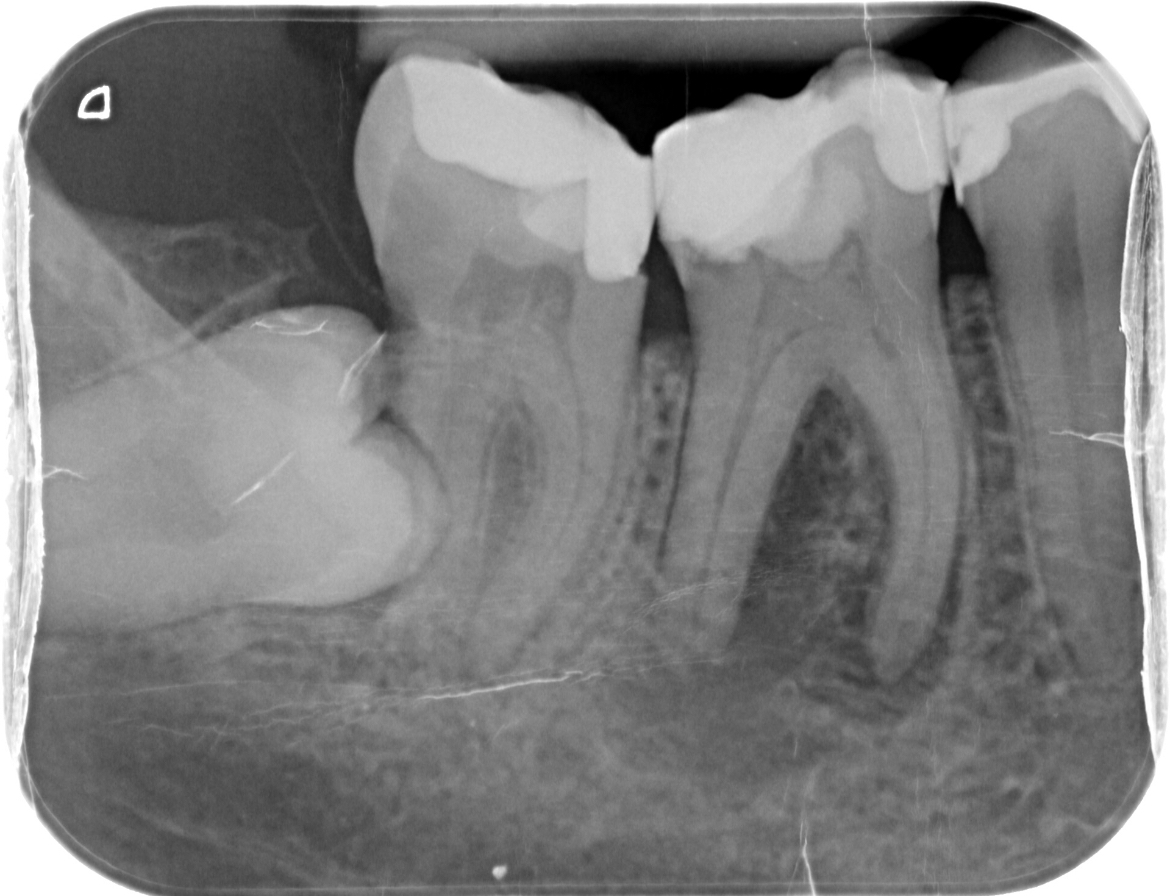

Wie kan mij helpen. Na lang uitstellen heb ik toch maar een afspraak gemaakt bij de kaakchirurg ingepland om mijn verstandskies eruit te halen die dwars ligt. (23 februari) De kiest daarnaast blijft staan en in de andere kies die daar naast staat zou een ontsteking zitten in de wortelpunt. Ik schrok heel erg van de kosten dus twijfel nu wat te doen. Of een wortelkanaalbehandeling of door de vele vullingen die al in deze tand zitten deze ook maar te trekken. Ik ben erg onzeker over mijn gebit door alle vullingen die ik heb in met name de kiezen. Aan de andere kant van mijn gebit is namelijk ook al een kies getrokken omdat deze gewoon heel zwak was en constant afbrak.

Ik hoop dat ik nog wel even met mijn tanden kan doen. Wat vind je op dit moment van de foto?

Zie je een grote ontsteking? Of kan dit nog behandeld worden met een antibiotica kuur.

Verstand kies verwijderen, wkb 46 ( eerste grote kies flinke ontsteking niet met AB kuur goed te krijgen) later kroon ( als u kiest voor behoud met vaste voorzieningen).....